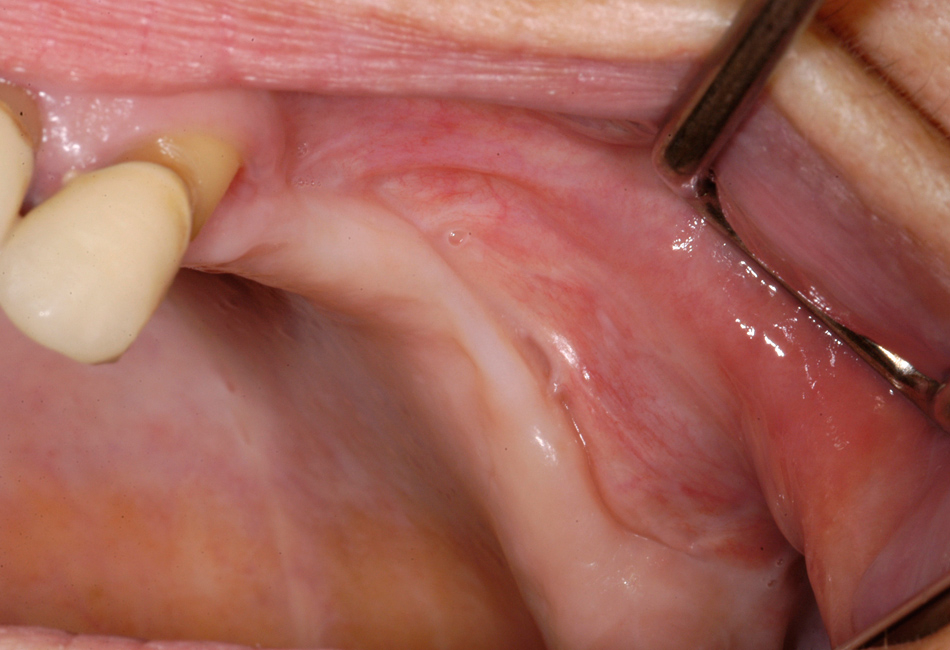

Figure 3

A Female patient with BRONJ of the right anterior mandible associated with periapical infection of the canine. The clinical picture shows no exposed bone, but signs of infection of the surrounding soft tissue and periodontal pus discharge.

B The same patient as figure 3A. Intraoperative view shows clearly the necrotic bone area in contrast to the vital bone in the left mandible. The necrotic area is surrounded from granulation tissue. Bone appears green-greyish.

Exposed bone was observed in only 74% of patients; 23% of patients presented with a fistula, but without clinically evident exposed bone (only radiologically evident affected bone) (fig. 3a and b). All of those patients except one were treated surgically; therefore, the diagnosis of osteopathology of the jaw was also affirmed clinically.